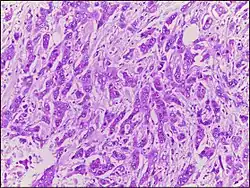

| Micrograph of breast tissue with ductal carcinoma. H&E stain. |

Ductal carcinoma is a type of tumor that primarily presents in the ducts of a gland.[1]